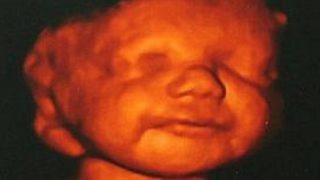

เมื่ออัลตราซาวด์ทารกที่พิการตั้งแต่อยู่ในครรภ์ กลับพบรอยยิ้มที่ทำให้แม่ตัดสินใจ...